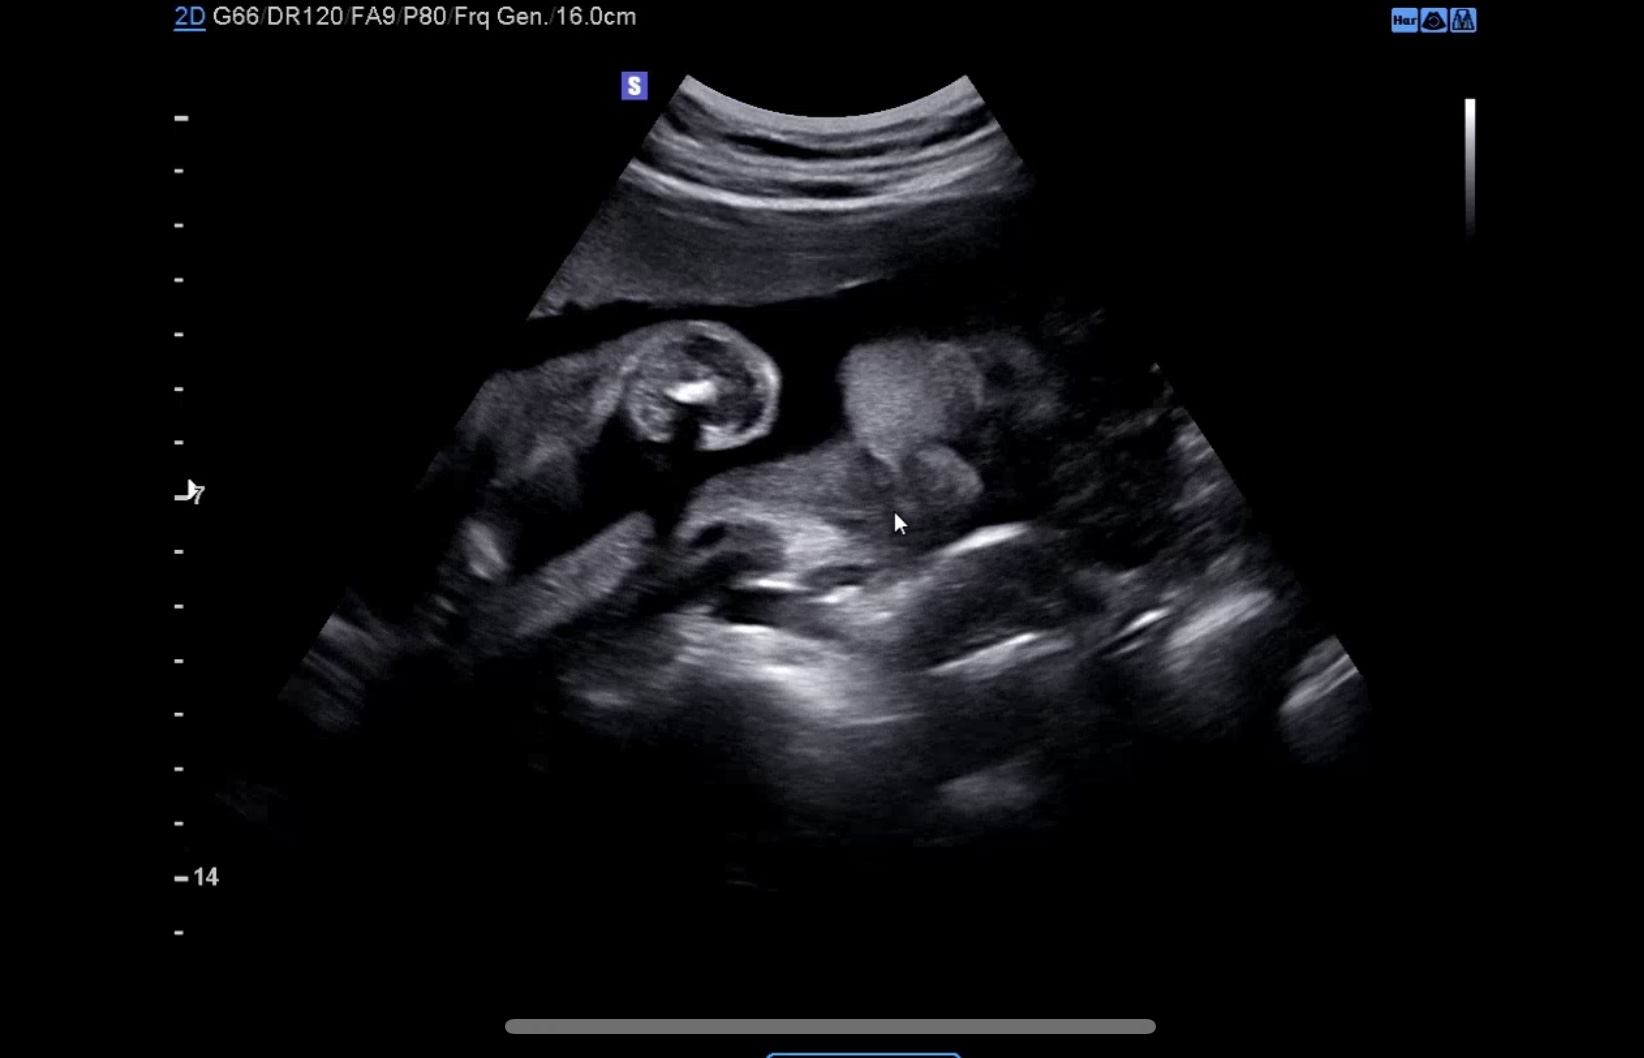

24주 6일째.

경부 길이와 강도를 먼저 재고 아기 배 초음파도 함께 봤다.

안타깝게도 앞 부분이 다 짤렸다;;

게다가 수치 나오는 왼쪽 부분도 짤림ㅠ

경부 길이는 3.5로 지난번 보다 좀 더 길어졌고, 강도도 88%로 아주 좋은 상태라고 했다.

끼끼도 24주 크기로 잘 크고 있다고 한다.

무게도 700g을 넘었다고..

근데 끼끼도 얼굴을 보여줄 생각이 없나보다ㅠ

등 쪽 자궁벽에 얼굴을 처박고(?) 있어서 얼굴을 볼 수 없었다.

마우스 커서 있는 쪽이 입술, 그 바로 위가 코..

처박고 있는 얼굴이라 얼굴이 전체적으론 안 보여서 모양새가 좀.. ㅋㅋ